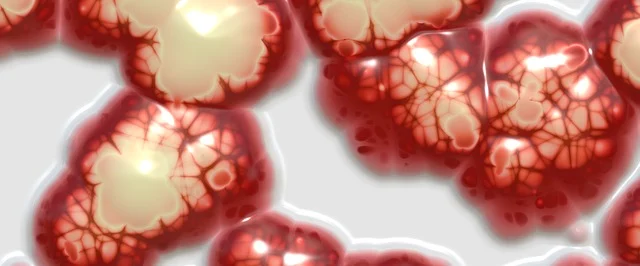

반응성 세포변화란 세포가 염증, 감염, 자극 등의 원인에 반응하여 일시적으로 변형된 상태를 말합니다. 이는 자궁경부세포검사(Pap smear)에서 흔히 나타나는 결과 중 하나이며, 대부분은 양성(비암성)입니다.

자궁경부세포검사에서 발견되는 반응성 세포변화는 자궁경부에 생긴 염증이나 감염, 호르몬 변화 등의 반응으로 세포의 형태나 배치에 약간의 변형이 생겼다는 의미일 뿐, 곧바로 자궁경부암을 의미하는 것은 아닙니다.